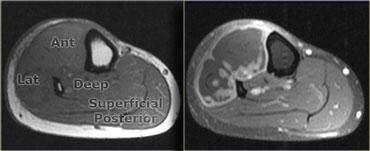

Ở cẳng chân có bốn khoang: khoang trước, khoang sau sâu, khoang sau nông và một khoang ngoài nhỏ.

Hình ảnh T1W bên trái của bệnh nhân một tháng sau chấn thương.

Trên hình ảnh sau tiêm Gadolinium, có thể thấy hoại tử ở khoang trước và khoang ngoài.

Khoang sau bình thường.

Bên trái là hình ảnh T2W của một bệnh nhân bị hội chứng khoang bên mạn tính.